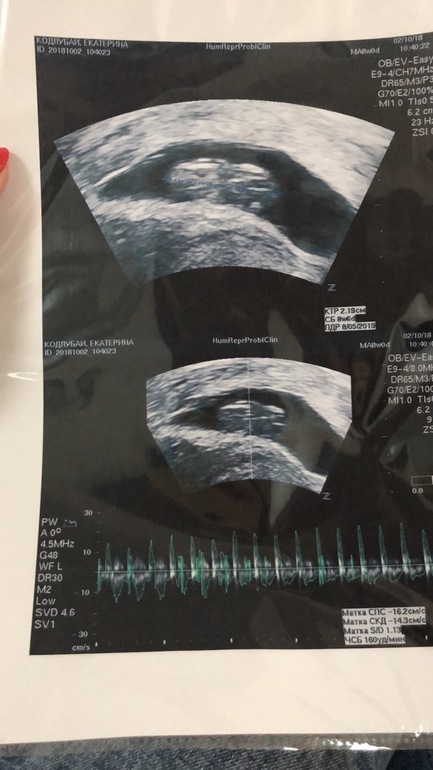

Растёт моя кроха))))

Всё о нашей беременностиВот такие мы уже большие))))

Опережаем на неделю)))

По переносу 8 недель, по узи 9 недель! А почему не есть хорошо! Моя гиня наоборот говорит что хорошо все) мне на 23 число назначено

Я уже сама запуталась)))) мне программа выдаёт 9 недель, но это акушерские я так понимаю, эмбрио на 2 недели меньше, а по узи на неделю больше)))) короче путают они меня, главное что все хорошо 👌

Узисты считают по акушерскому сроку, т.е от последних М.У меня тоже на 3 дня опережает по узи, т.е например делала в 8 и3 акушерских, а по узи ставят, что соответствует 8 и 6